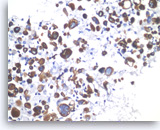

Acinar cell carcinoma,

Pancreas FNA, Cell Block.

The tumor cells are also focally positive for trypsin. Negative staining is found for neuroendocrine markers CD56, synaptophysin, and chromogranin, excluding the diagnosis of a pancreatic endocrine neoplasm. Despite the relatively bland appearance and the close resemblance to pancreatic endocrine neoplasms, acinar cell carcinomas are relatively aggressive tumors.

40X